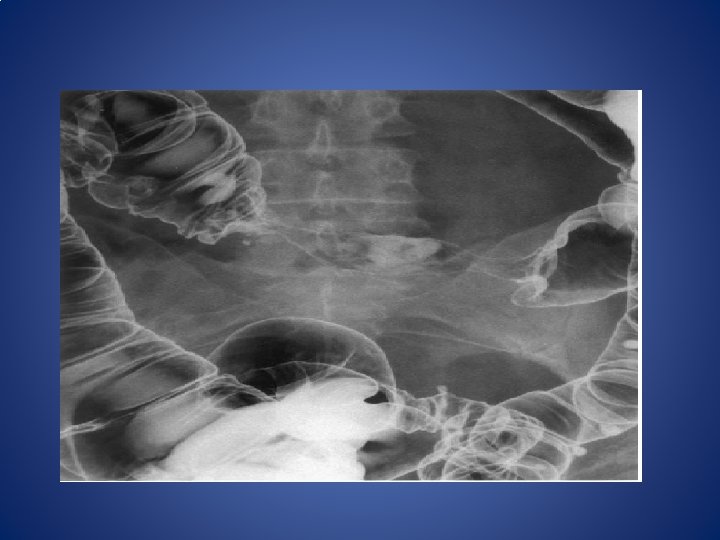

INVESTIGATIONS • 1)ABDOMINAL EXAMINATION • Normal in early cases • Advanced annular tumour at rectosigmoid junction-----signs of int. obstruction. • Palpable liver----metastasis • Ascites ---secondary deposits to peritoneum

• 3)PROCTOSIGMOIDOSCOPY • Will always show carcinoma----rectum should be empty before hand • 4)BIOPSY • Using biopsy forceps via a sigmoidoscope---will confirm the diagnosis • 5)COLONOSCOPY • To exclude other tumours. • 6)ultrasound